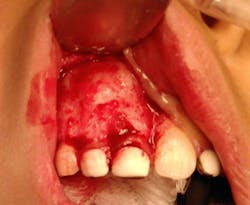

The patient, under intravenous anesthetic, underwent enucleation of the lesion with simultaneous extraction of primary teeth D and E. An intraoral approach was used, the labial cortex was removed, and the mass was removed intact via simple enucleation (figures 3 and 4). The crowns of permanent teeth nos. 7 and 8 were visualized within the cavity of the enucleated mass. No grafting was performed, and the wound was closed primarily in simple fashion.